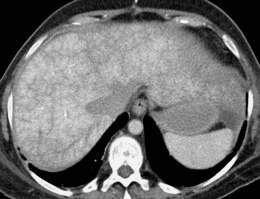

- Tomografía computarizada o resonancia magnética del abdomen

- Ecografía del hígado